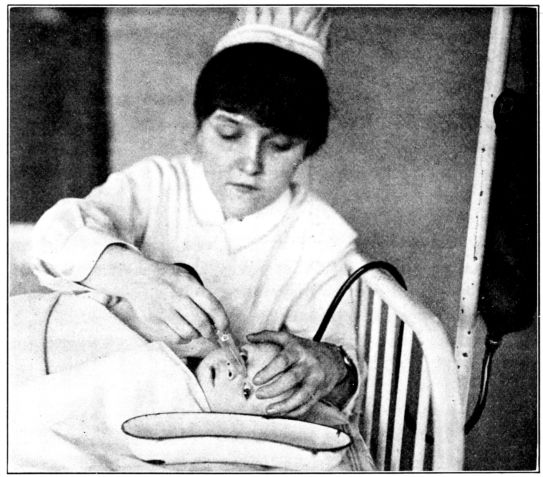

| 187. | Irrigating the eye with a blunt nozzle | 536 |

| 188. | Method of holding baby for treating gonorrhœal ophthalmia | 537 |